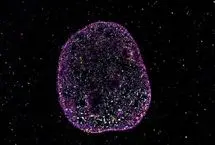

درون هر سلول، دیانای به «حوزههای بستهبندی» نانومقیاس تا میخورد که گرههای حافظه فیزیکی ایجاد میکنند، واحدهایی که…